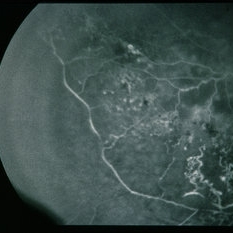

BRVO - Massive Exudate from Collaterals

Feb 24 2014 by David Callanan, MD

66-year-old female with BRVO - massive exudate from collaterals, 20/70 OD; 20/25 OS in 1985; +HTN, glaucoma; 20/200 OD 1987.

Condition/keywords: branch retinal vein occlusion (BRVO), collaterals, exudate